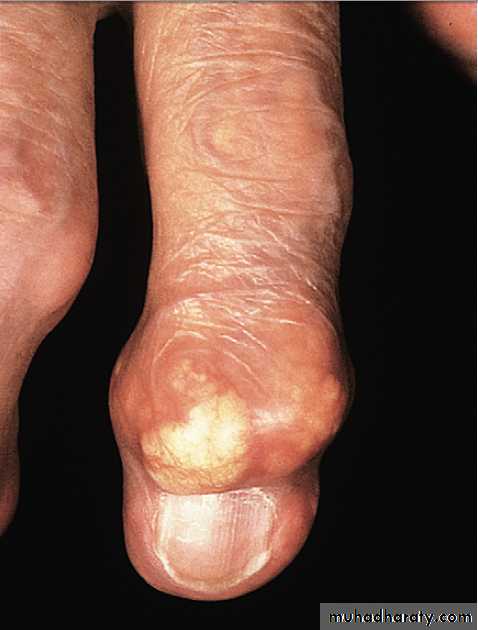

In tophaceous gout, well-defined punched-out erosions may occur .